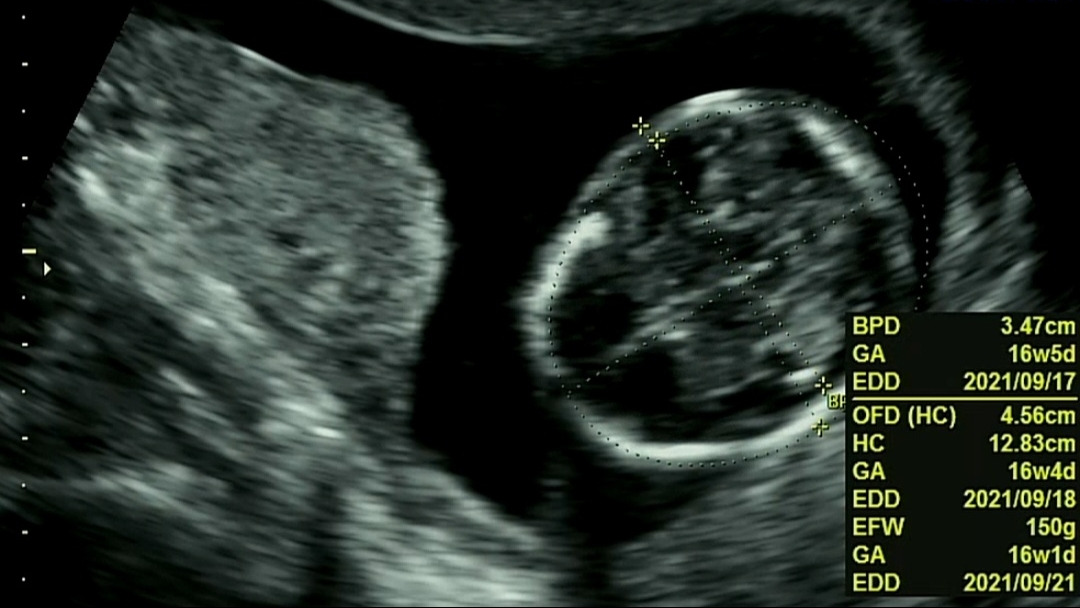

덕순이의 작은 머리

16주 차

의 아기는 존재감을 나타내기엔 아직 너무 작았다.

머리 둘레 12.83cm, 허벅지 뼈 2.09cm, 추정 몸무게 150g...

대충 짐작해도 한 손바닥에 폭 잠길만한 크기였다.